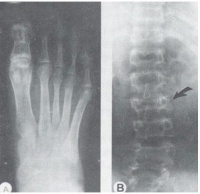

骨骼畸形有四肢和指趾细长(蜘蛛指趾),易误认为是马凡氏综合征。X线检查可见骨质疏松,椎体背侧呈双凹形,以及脊柱侧弯等。眼部症状多有晶体脱位,多发生于3~10岁间,常伴青光眼视网膜剥离。血栓形成可发生于任何器官,约50%的病例发生过一次或多次血栓栓塞发作,颅内血管、冠状动脉肾动脉、肺血管、皮肤血管等均可有血栓形成,并出现相应的症状。神经系统症状较明显,可有智力低下,惊厥发作。多发性脑血管意外可致偏瘫假性球麻痹,也可有精神症状。其他症状也可见到,如颧部潮红、皮肤大理石花纹、皮肤薄、毛发稀少易折,凝血酶原减少肌病等。

本病需与马凡氏综合征鉴别。二者的共同点是晶体异位、蜘蛛指趾、心血管症状。但遗传方式和病情发展不同。本病为隐性遗传马凡氏综合征是常染色体显性遗传,指趾细长自初生即可见到;而同型胱氨酸尿症在初生为正常,数年后骨骼的生长不成比例,而四肢加长,此外还有血栓栓塞症状,骨质疏松,椎骨有双凹畸形等。更重要的是马凡氏综合征没有本病那种生化代谢异常。